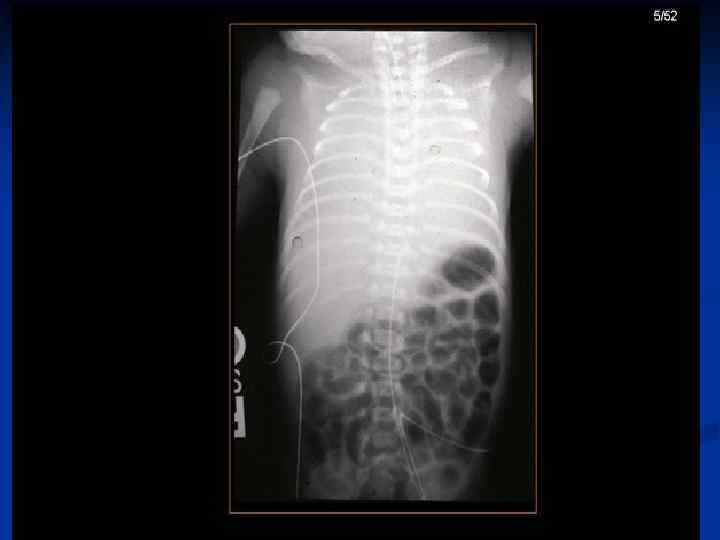

Chest X-ray of the infant 3 days old Reticular granularity of lung fields called "ground-glass” appearance with airbronchogram as the air passages show well against poorly aerated lung.

RDS